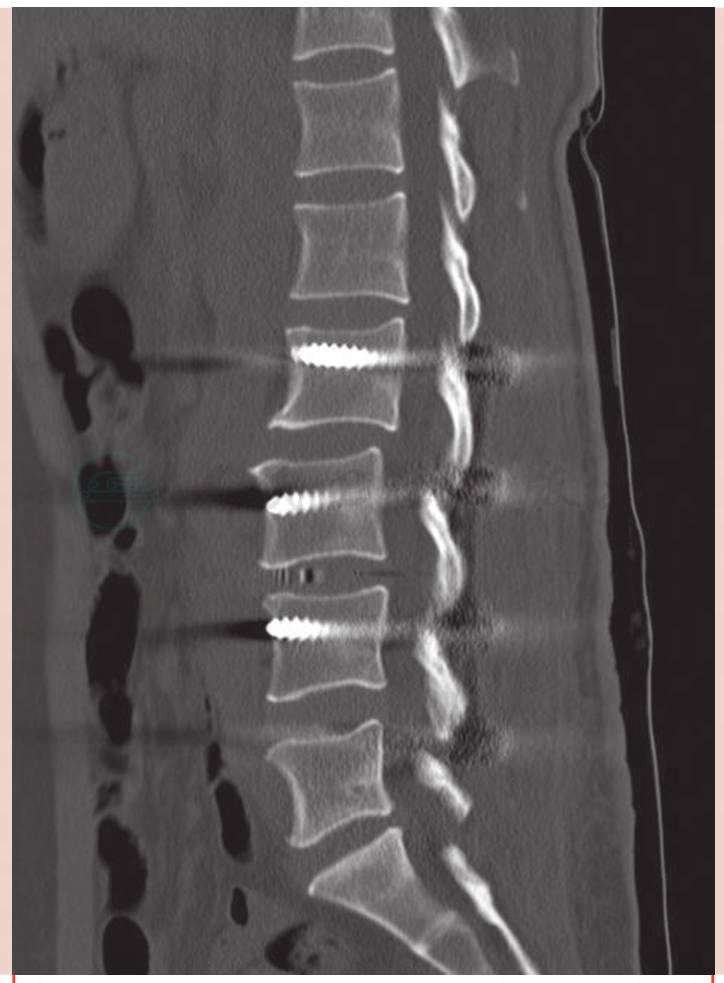

术前CT示:腰椎侧弯(图2)、退行性变、L3椎体滑脱(图3、图4)。L3-4椎间盘突出右侧椎间孔变窄(图5)。

图3 术前CT矢状位示L3椎体滑脱

图9 术后CT矢状位示腰椎曲度良好